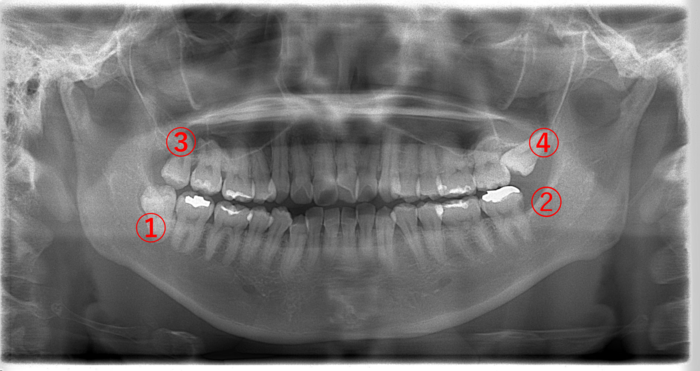

| 主訴 | 右上の親知らず(画像③)が急に痛み始めた。 |

画像③の親知らずを見てみると黒く透けています。虫歯になると歯が溶けて柔らかくなるので、レントゲンでは黒く写ります。虫歯が歯の神経に達すると痛みが強くなります。

③の親知らずを抜歯して、①の親知らずも抜きたいところですが、③の親知らずの痛みが強いこともあり、一緒に抜歯せずに後で③の親知らずを抜く方が良いと説明しました。

| 主訴 | 左上の親知らず(画像④)が痛くて我慢ができない。どちらかというと鋭い痛みがある。 |

画像④の親知らずに大きな黒い虫歯の影が見えます。虫歯になると歯が溶けて柔らかくなるので、レントゲンには黒く写ります。

画像④の親知らずを抜いた場合、下の➁の親知らずを抜かずに放置すると上に伸びて来て、かみ合わせの邪魔をすることがあります。

そのため、上下同時に親知らずを抜くか、④の親知らずを抜いてから➁の親知らずを抜くか、どちらかになります。また、右上④の親知らずがないため、②と④の抜歯後、①の親知らずを抜きます。

| 主訴 | 数日前より右下の親知らず(画像①)周りの歯ぐきが急に腫れ始めて、みるみる内に膨らんだところを誤って噛んでしまい、出血が止まらなくなった。 |

今後、画像➁の親知らず周りも腫れることが予想され、同じように噛んで出血するというパターンも考えられるため、できれば4本とも抜いた方が良いでしょう。

初回は、止血処置、抗生剤の投与と服用で腫れを引かせ、後日、画像①の親知らずを抜きました。

画像①の親知らずが真横に生えていて、手前の⑤の歯との間に隙間があります。ここに食べかすが入り込むとどんなに歯を磨いても取れません。取り除かれない食べかすが腐り、口臭の原因となっていると思われます。

早めに抜くことで口臭はなくなると思われます。また➁の親知らずも汚れが溜まりやすそうなので、口臭の原因となる可能性があります。

そして、③の親知らずは、黒く透けていることからして虫歯になっています。

この場合、右側上下(①と③)と②の親知らずを抜くことをオススメします。

④の親知らずは、歯ぐきが被ったまま出てこないのであれば積極的に抜かず様子を見ても良いですし、もし全部抜いてスッキリしたいのであれば、抜いた方が良いと思います。

画像①と③の親知らずは、真っ直ぐ生えていますが、2〜3日前より①の親知らず周りの歯ぐきが腫れて痛いとのことでした。

奥まで磨くのは困難と判断し、①の親知らずを抜くことにしました。また説明として、対合歯がない③の親知らずは後々下に伸びてくることを考えると早めに抜いた方が良いことを伝えると同時に抜きたいと希望されたため、初診当日に①と③の親知らずを2本同時に抜きました。